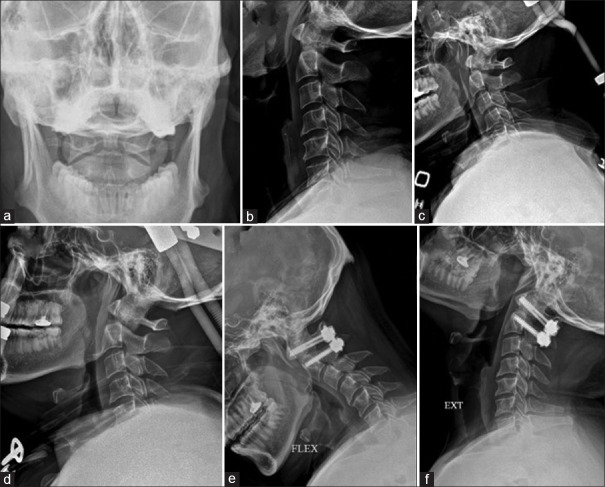

Introduction: The options for the management of type II odontoid fractures in young patients include anterior screw fixation, posterior spinal fusion, or halo-vest immobilization (HVI). However, there is a recent trend away from nonoperative management and an increase in primary operative stabilization across several centers. Hence, our study aims to compare the functional and radiological outcomes of type II odontoid fractures in young patients managed with HVI and surgery.

Materials and methods: A retrospective analysis of 70 patients with type II odontoid fracture who were managed in our institution with a mean age of 47 years was included in our study. The clinical details included the Neck Disability Index (NDI), Visual Analog Scale (VAS) for neck pain, and S-Range of Movement (ROM)-Neck score. Radiological details included union status, atlanto-dens interval, amount of displacement and angulation, and transverse ligament injury. Both the clinical and radiological parameters were compared between the patients who underwent HVI (n = 28) and surgery (n = 42).

Results: The mean ± standard deviation follow-up duration was 4.2 ± 2.5 years in the HVI group and 3.8 ± 2.7 years in the surgery group. Of the clinical parameters, the S-ROM-Neck score was significantly better in the HVI group than in the surgery group (P < 0.001). The length of hospitalization was much shorter in the HVI group (P < 0.001). There were no differences in NDI, VAS for neck pain, and other radiological parameters.